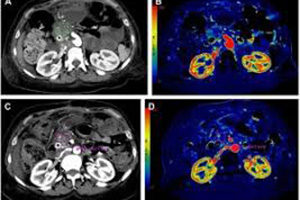

Компания Star-Test, предоставляющая диагностические услуги в Стамбуле с 1993 года, располагает самыми передовыми радиологическими устройствами с технологией.